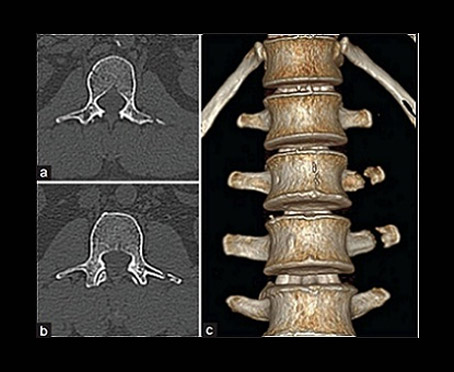

Heart-rate independent very high temporal resolution of 83 ms. Very high spatial resolution of 0.33 mm. Adaptive ECG-Pulsing™, heart beat controlled dose modulation, reacts to any changes and abnormalities of the heartbeat in real time. Adaptive table speed reduces acquisition time and dose at higher heart rates. Adaptive 4D spiral scan - For whole brain perfusion and dynamic CT angiography. Dual Energy applications - Simultaneous acquisition of two data sets at different kVs. This unique capability enables us to characterize stones, give excellent angiograms, detect gout, detect pulmonary embolism, Direct angiography that provides excellent delineation of vessels, single pass myocardial perfusion, plaque on/off facility in angiography and other applications that are not available in other CT scan machines. X-CARE - We care for you and have installed X-CARE facility. This is installed for first time in India and it reduces radiation dose to lens of eye, thyroid gland, breast & gonads while maintaining excellent image quality. All X-ray and CT installations are AERB (Atomic Energy Regulatory Board) approved. This shows our commitment in not only providing you the best of technology but also to ensure that the radiation dose is kept to the minimum.

• Multiphase, multi-planar imaging